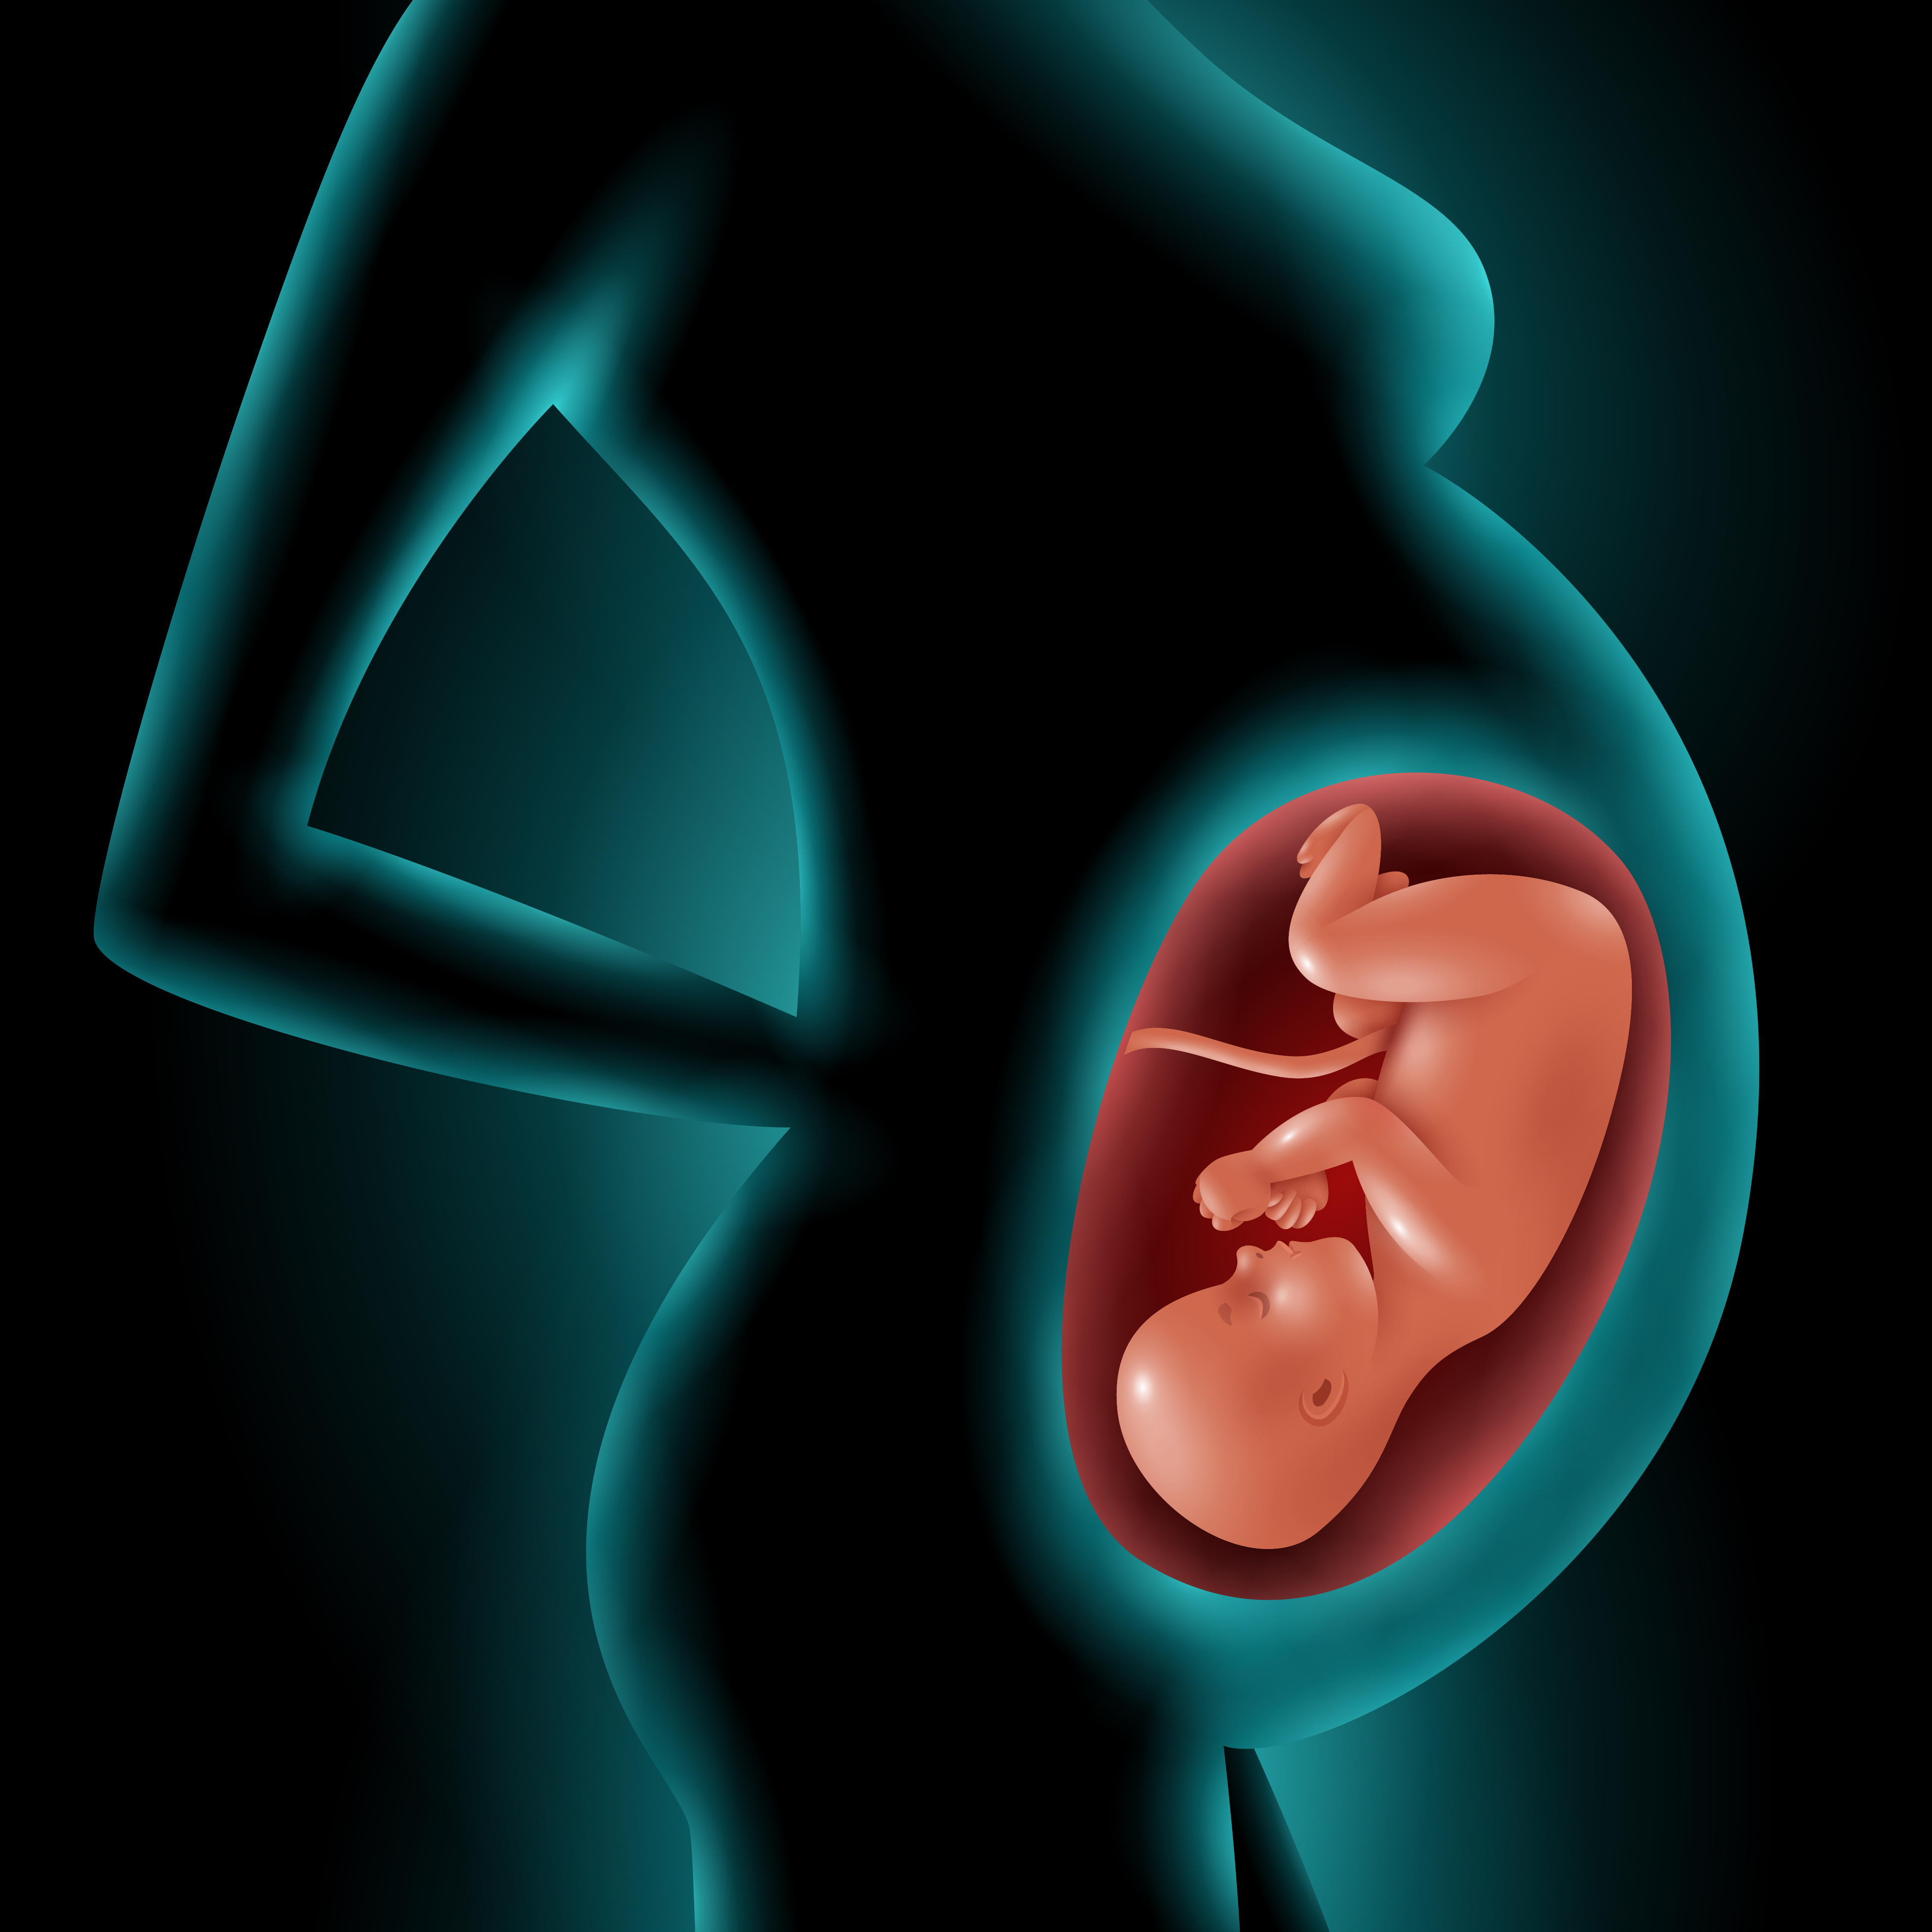

Фотография Плода В Животе

Фотография Плода В Животе 113 фотографий